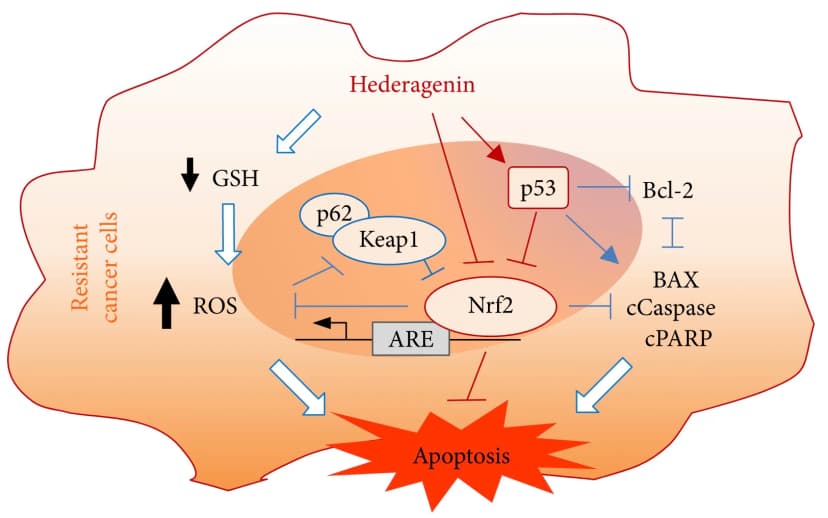

The 8+ Benefits of Hederagenin (with Sources and Derivatives)

5 min read